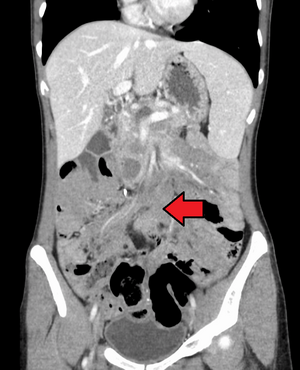

DesmoidTumorCTCorMark.png

ورم رباطي كما هو موضح في الاشعة المقطعية